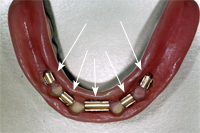

Die Prothese wird vom Techniker ebenfalls am gleichen Tag umgebaut. Auf der Innenseite der Unterkieferprothese sind die fünf Steghülsen sichtbar (Abb. 4), welche die Vollprothese stabil, sicher und unverrückbar festklemmen.